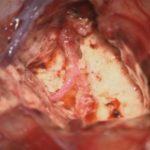

No.’25_82 手術前1

No.’25_82 手術前2